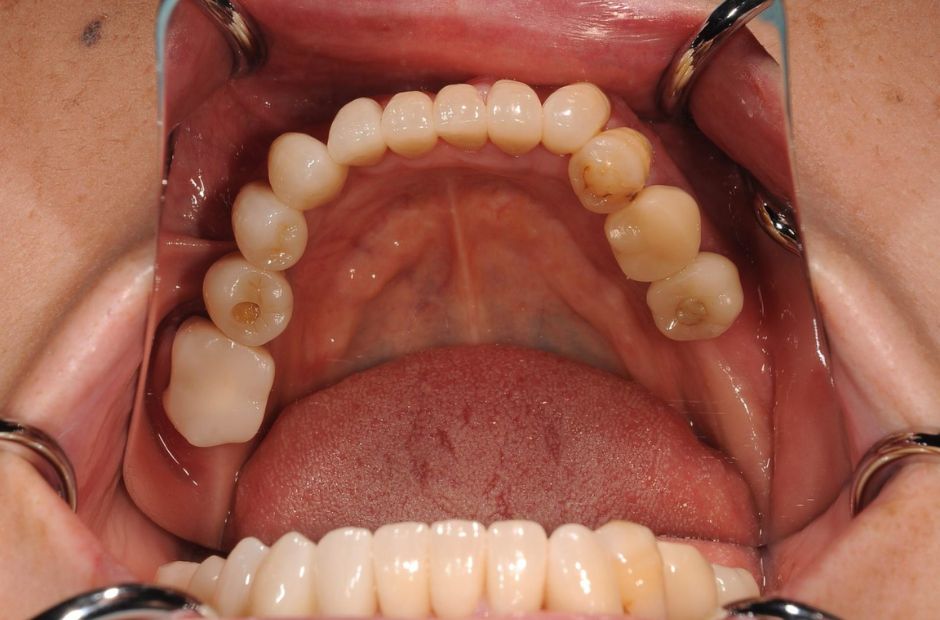

case.02

差し歯とインプラントの治療

若年の患者様が前歯の審美性について相談に来られました。差し歯とインプラントの組み合わせにより、自然で美しい笑顔を実現しました。患者様は見た目の改善と機能性の向上に大変満足されました。